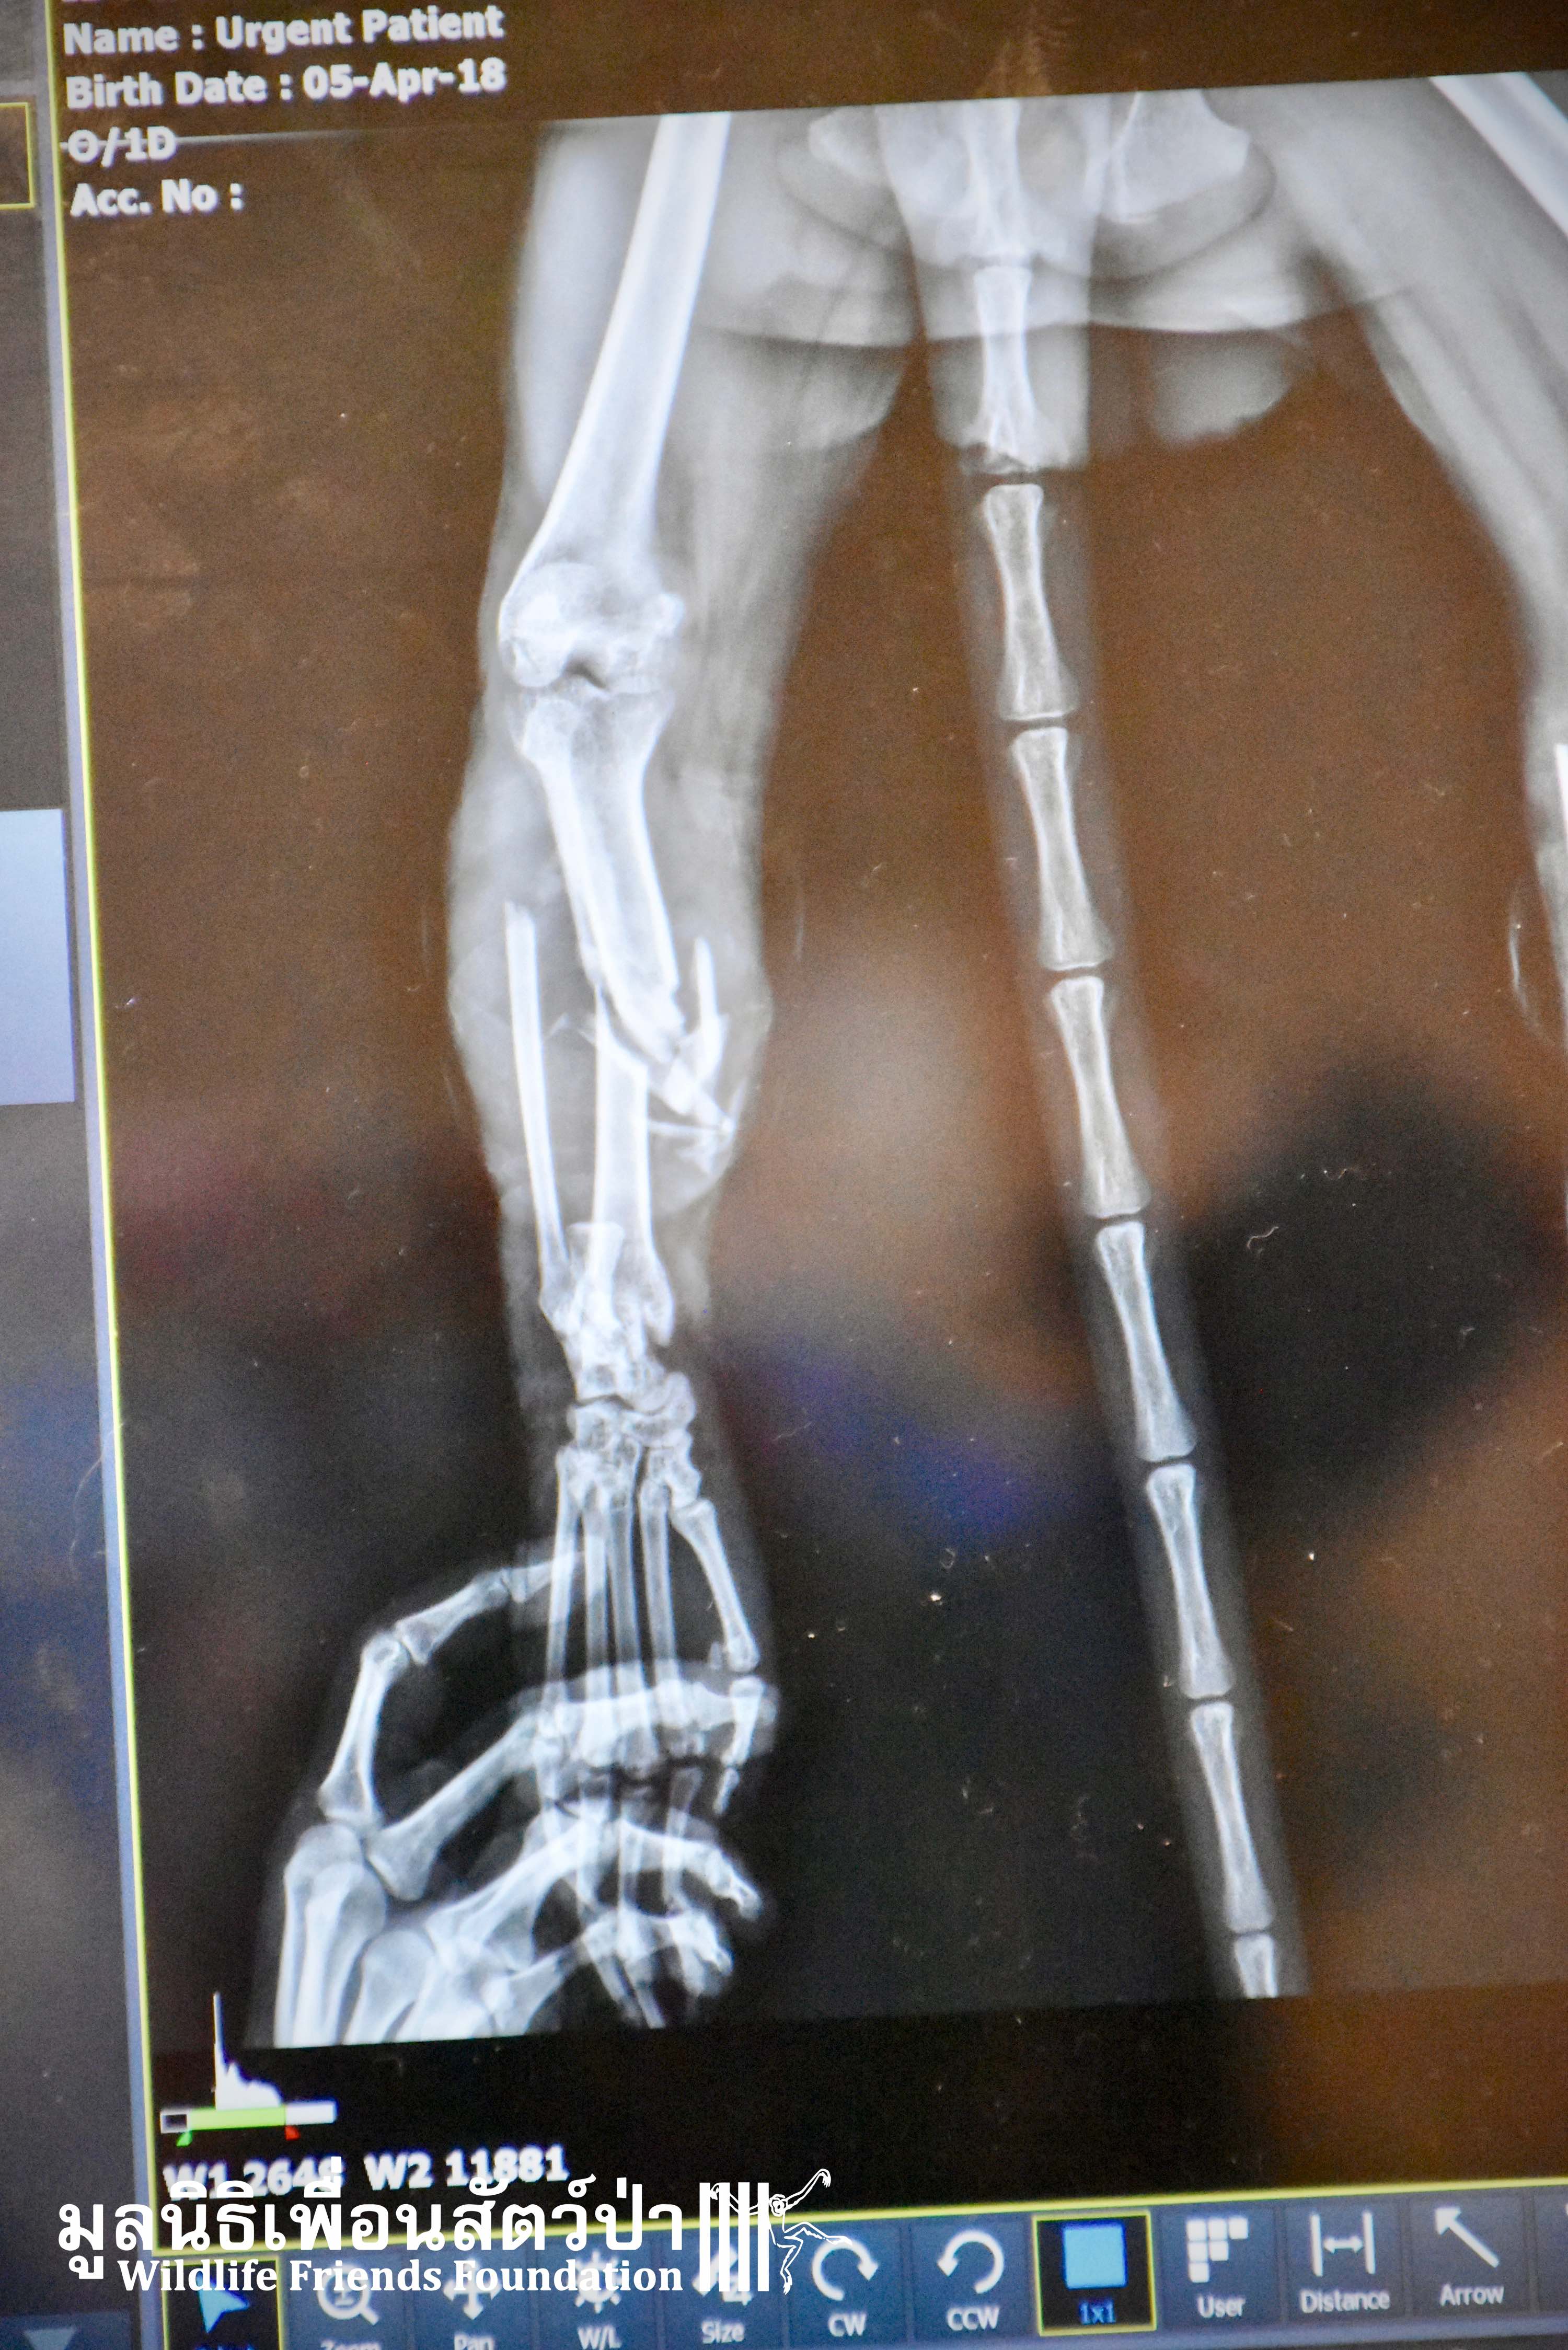

Last week we received a call from help from some veterinary colleagues at a pet hospital in Bangkok who had received a severely injured adult male long-tailed macaque (Macaca fascicularis) who had been found by a lady in Ayutthaya. She informed the staff at the Crystalpet Hospital in Bangkok that the monkey had been dumped at the temple as an unwanted pet. She had seen him unable to move sat in a shallow pond for sometime and got worried. The lady captured him and rushed him straight to the clinic who asked if we could house him at the WFFT Wildlife Rescue Centre. After a full health check it was found the ‘Jok’ as we have called, had two very badly broken legs. We do not know what caused this but it was sure a huge incident as the breaks in his legs were very severe as you can see from the x-rays. Two days ago the WFFT Vet Team were joined by a group of other veterinarians, orthopaedic surgeons, who came to fix his legs using metal plates and pins. The surgery went well and for now Jok is recovering well at the WFFT Wildlife Hospital. We will keep you posted on his progress.